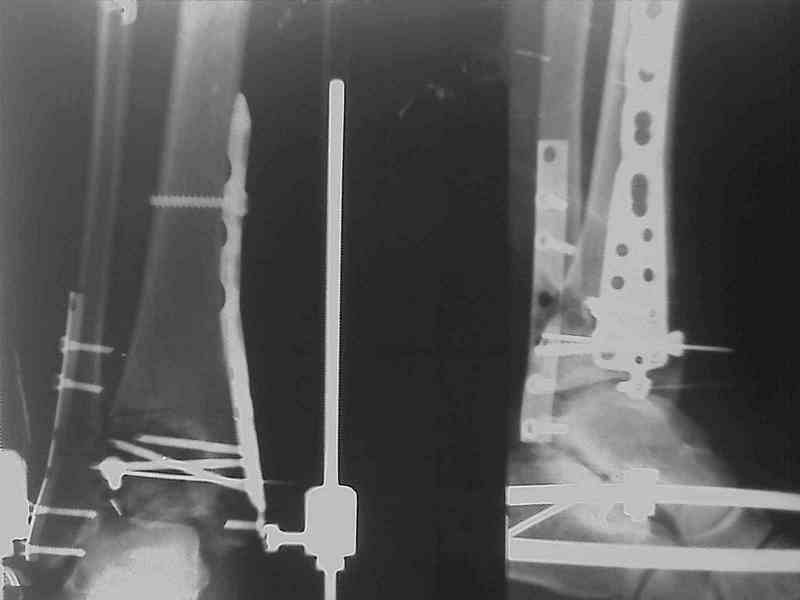

Добавлены КТ снимки. Прошу прощения за качество.

С уважением, Коваленко А.Н.

Снова приветствую вас, коллеги. К моменту вступления в обсуждение аксакалов, операция была, увы, выполнена(31.10.07.) Начали с доступа к наружной лодыжке, произвели ее фиксацию спицами, развернули кусок заднего края, наложили дистрактор, затем произвели дистракцию, фиксацию спицами дистального эпиметафиза б/бк,Рентгено-контроль. синтез наружной лодыжки 1/3пластиной. из двух коротких разрезов сформирован канал под медиальную тибиальную пластину LCP. Края ран ушиты без натяжения. Прочувствовать жесткость фиксации винтами с угловой стабильностью не удалось, поэтому дистрактор оставлен на энное время.

На представленных R-снимках не окончательный вид после остеосинтеза. Дистальная опора давила на стопу, пришлось ее сместить проксимально, в рез-те чего, она закрыла щель сустава, последние снимки не информативны.